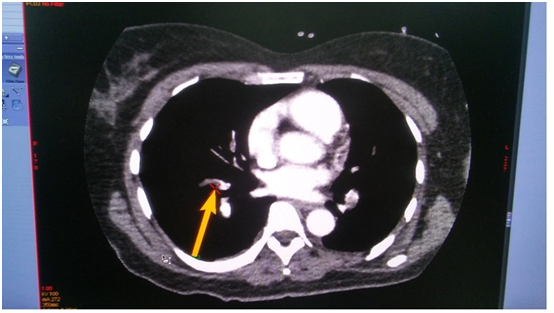

On the next day, at the day time, she felt progressive dyspnea. She was transferred to the intensive care department, where the suggestion of acute lung artery thromboembolic was taken, taken into account the character of dyspnea and extremely low level of blood saturation 60%, with weak response to oxygen therapy. The suggestion was approved by the chest tomography, where the thrombosis of both central lung arteries was revealed (Figure 1-4). After the short discussion among the colleagues, the procedure of thrombolysis was performed. We considered the extremely bad condition of the patient, weak response to oxygen therapy, young age and a kind of the operation. There were no pass to any cavity, no anastomosis, the inserted drainage system, to let blood flow out. Additionally, we had blood cell-save machine “Haemonetics Cell Saver 5+” (USA) to reinfuse blood and decrease blood loss.

Figure 4 (CT of thromboembolism in the right LA).